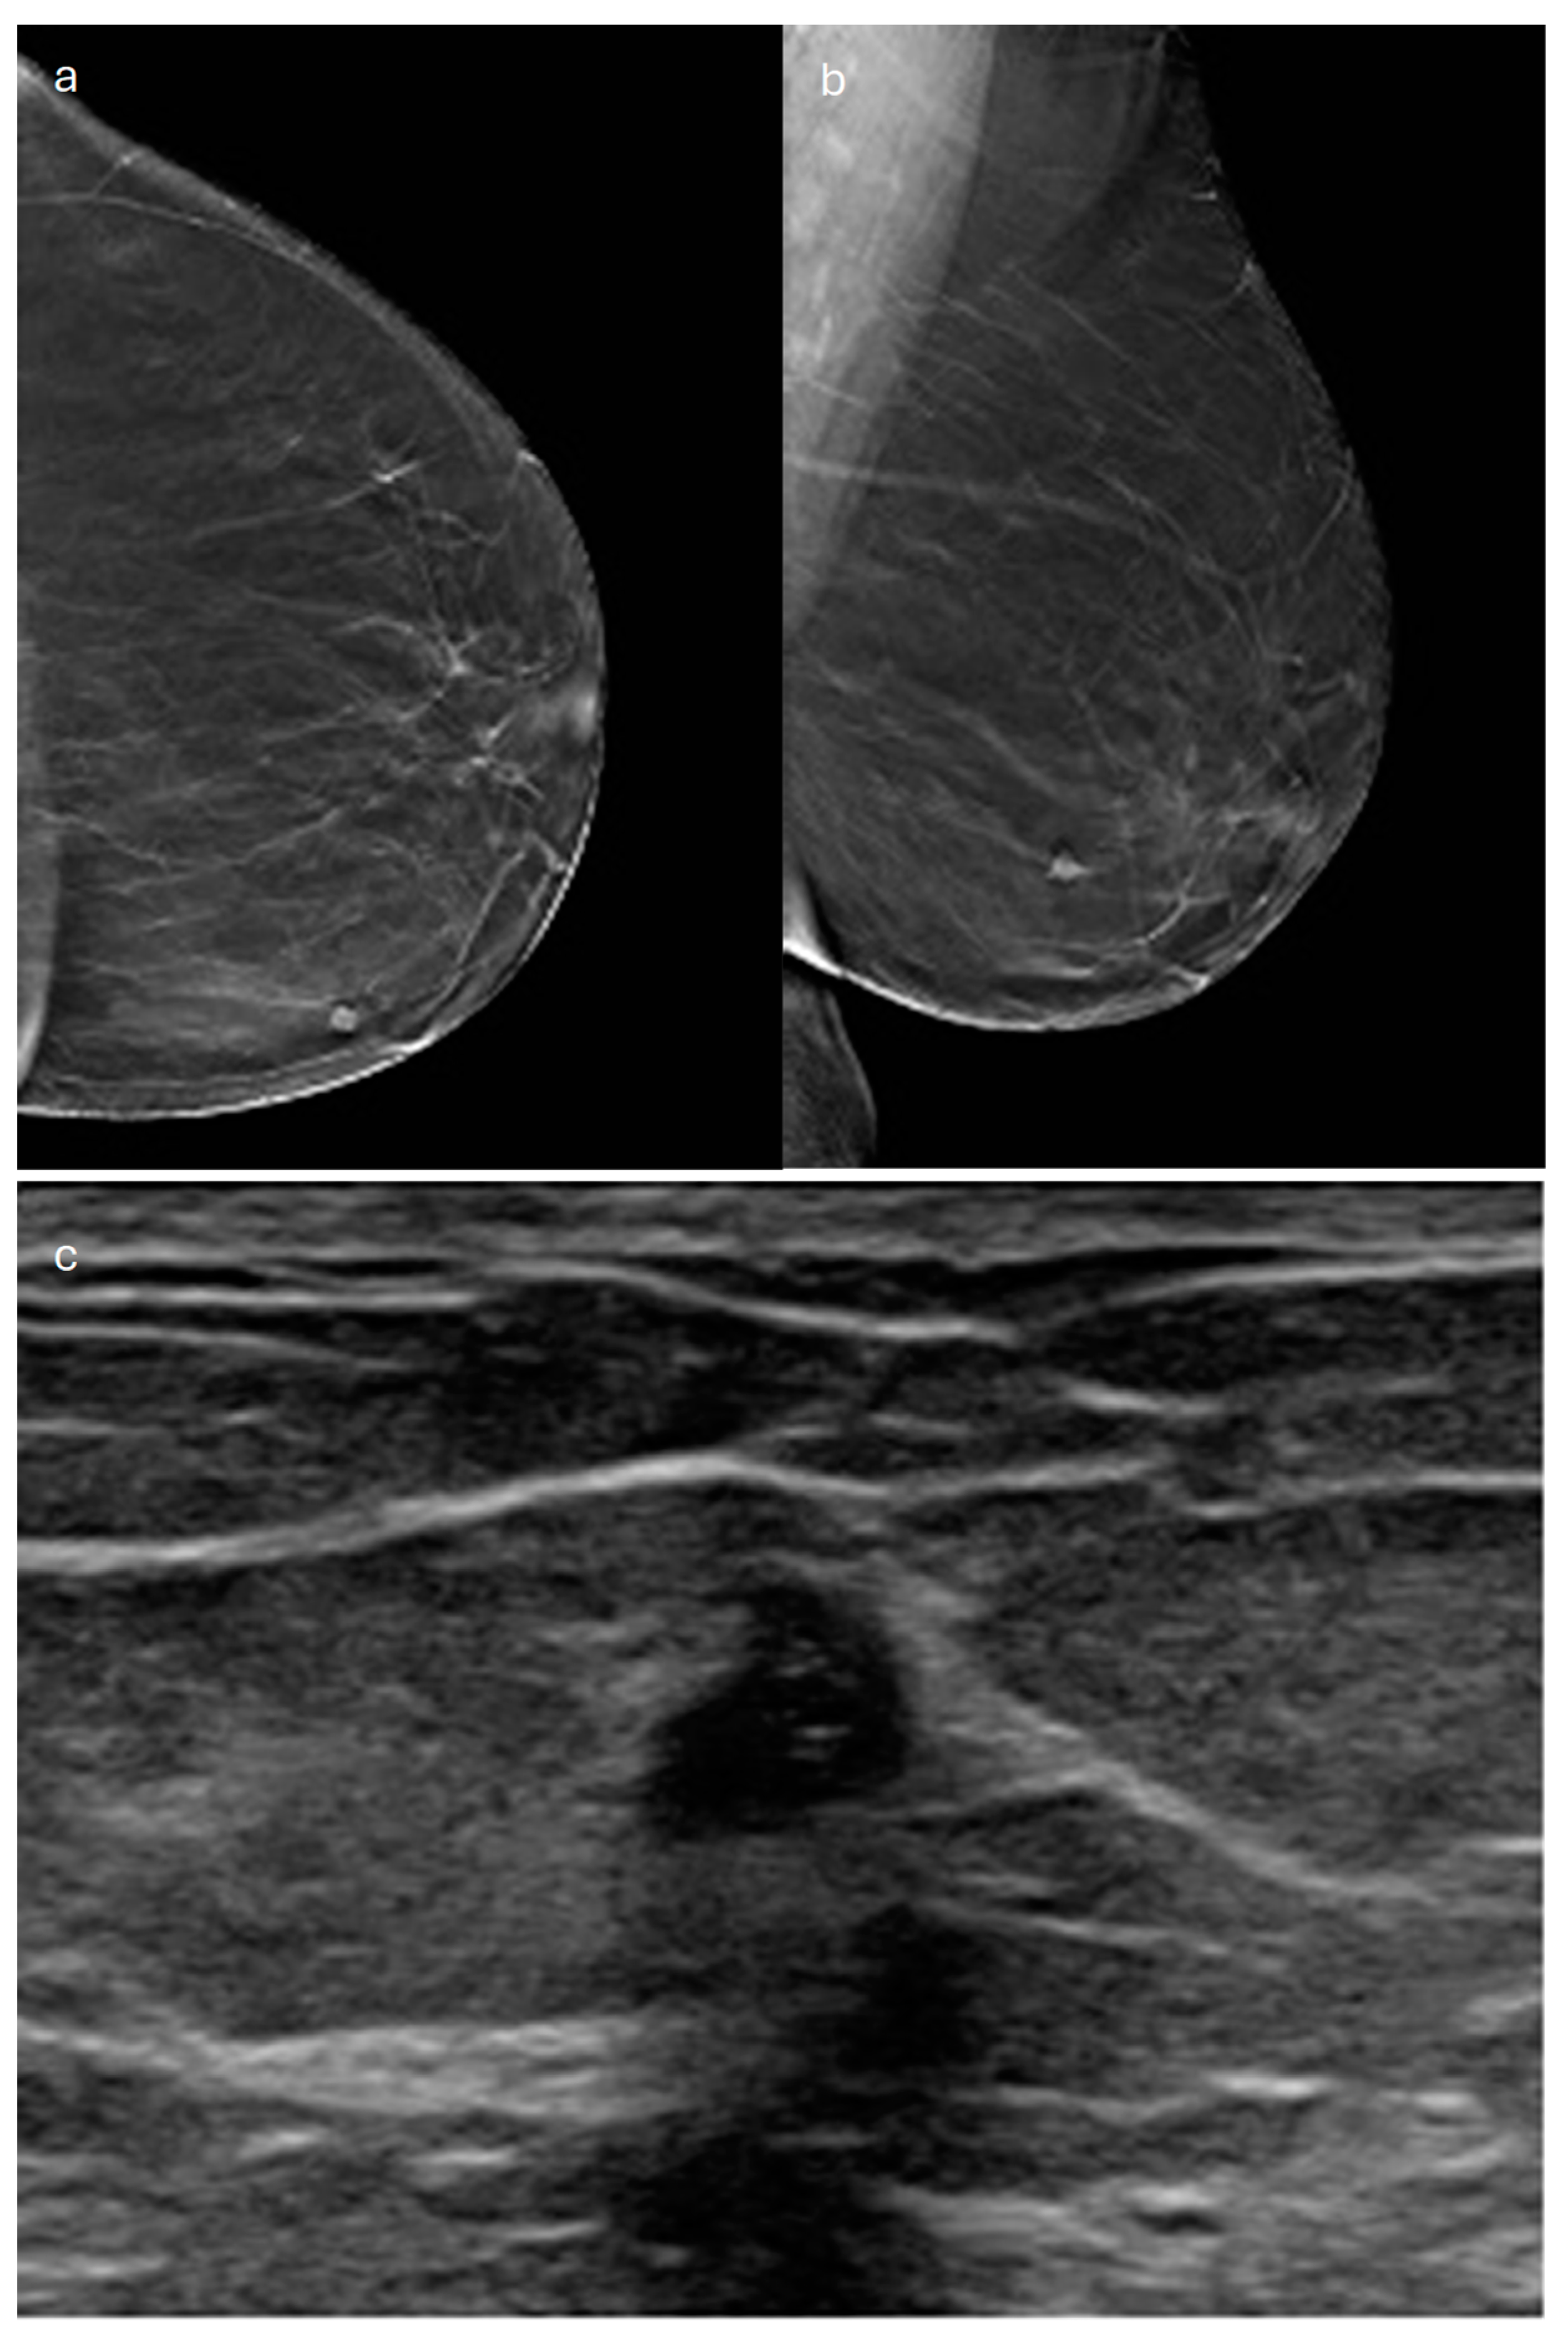

3. Tubular

- Harvey, J.A. Unusual Breast Cancers: Useful Clues to Expanding the Differential Diagnosis. Radiology 2007, 242, 683–694. [Google Scholar] [CrossRef]

- Sheppard, D.G.; Whitman, G.J.; Huynh, P.T.; Sahin, A.A.; Fornage, B.D.; Stelling, C.B. Tubular Carcinoma of the Breast: Mammographic and Sonographic Features. AJR Am. J. Roentgenol. 2000, 174, 253–257. [Google Scholar] [CrossRef]

- Linda, A.; Zuiani, C.; Girometti, R.; Londero, V.; Machin, P.; Brondani, G.; Bazzocchi, M. Unusual Malignant Tumors of the Breast: MRI Features and Pathologic Correlation. Eur. J. Radiol. 2010, 75, 178–184. [Google Scholar] [CrossRef]

- Ghai, S.; Muradali, D.; Bukhanov, K.; Kulkarni, S. Nonenhancing Breast Malignancies on MRI: Sonographic and Pathologic Correlation. Am. J. Roentgenol. 2005, 185, 481–487. [Google Scholar] [CrossRef]

- Yılmaz, R.; Bayramoğlu, Z.; Emirikçi, S.; Önder, S.; Salmaslıoğlu, A.; Dursun, M.; Acunaş, G.; Özmen, V. MR Imaging Features of Tubular Carcinoma: Preliminary Experience in Twelve Masses. Eur. J. Breast Health 2018, 14, 39–45. [Google Scholar] [CrossRef]